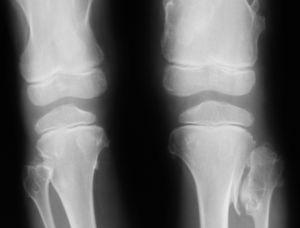

Figura 1. Múltiples osteocondromas en ambas rodillas.

Se presenta el caso de un niño de 6 años que acude a la consulta por dolor en la rodilla izquierda de 2 semanas de evolución que se ha incrementado en los últimos días, y se acompaña en ocasiones de cojera debido al dolor; no ha presentado fiebre ni otros síntomas y está realizando una actividad normal. A la exploración destaca dolor a la palpación de toda la zona interna de rodilla izquierda, leve protrusión del cóndilo femoral interno y discreta limitación por dolor a la extensión completa de la rodilla. El resto de exploración por aparatos es normal. Se trata de un niño, por lo demás sano, que ha seguido los controles de salud e inmunizaciones habituales con antecedentes personales de adenoidectomía y drenajes transtimpánicos a los 2 años, varicela a los 3 años y 3 episodios de bronquitis obstructiva a los 5 años. Se realiza estudio radiológico de serie esquelética que pone de manifiesto múltiples exostosis en metáfisis de huesos largos (fig. 1). No se encuentran lesiones costales, en pelvis ni en cráneo. Antecedentes familiares: varios miembros de la familia afectados de la enfermedad, ninguno de ellos ha tenido que ser intervenido ni ha malignizado (fig. 2). Se remite al servicio de ortopedia infantil donde se diagnostica, dados los antecedentes y la radiología, de exostosis múltiple familiar, y se adopta una conducta expectante. Para disminuir el dolor se recomienda reposo relativo e ibuprofeno. El dolor desapareció completamente en unos 15 días y se atribuyó a una contusión sobre una exostosis de la rodilla.